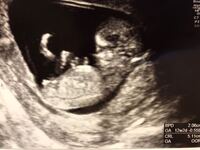

妊娠12週5日 12w5d の超音波 エコー 写真